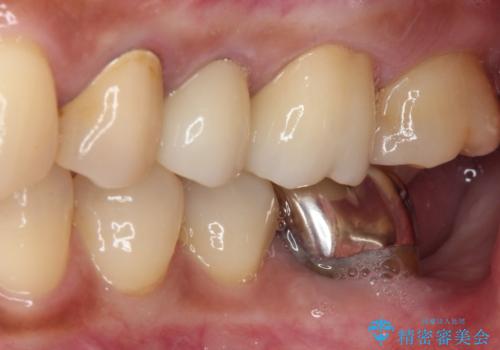

億劫に感じて治療を先延ばししていたそうですが、始めてみるとスムーズに治療が終わり、早く始めておけば良かったと仰っていました。

他にも加療の必要な歯があるので、定期健診を行いながら再開していく予定です。